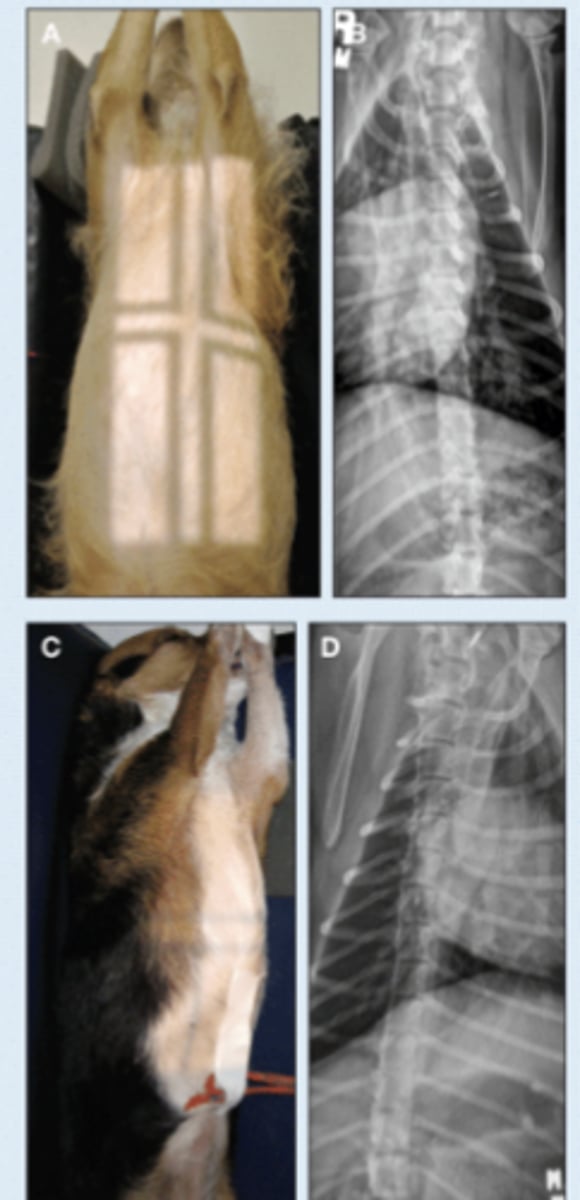

SM Animal Spine Lateral

SM Animal Spine VD

SM Animal Spine- Lateral Image

• Patient in lateral recumbency

• Center on region of interest - Cervical - CT junction

• Marker to indicate the laterality of patient

SM Animal Spine - VD image

• Patient in dorsal recumbency

• Centered on area of interest

• Angle beam toward thorax to image through caudal discspaces*

• Marker to indicate laterality of patient*